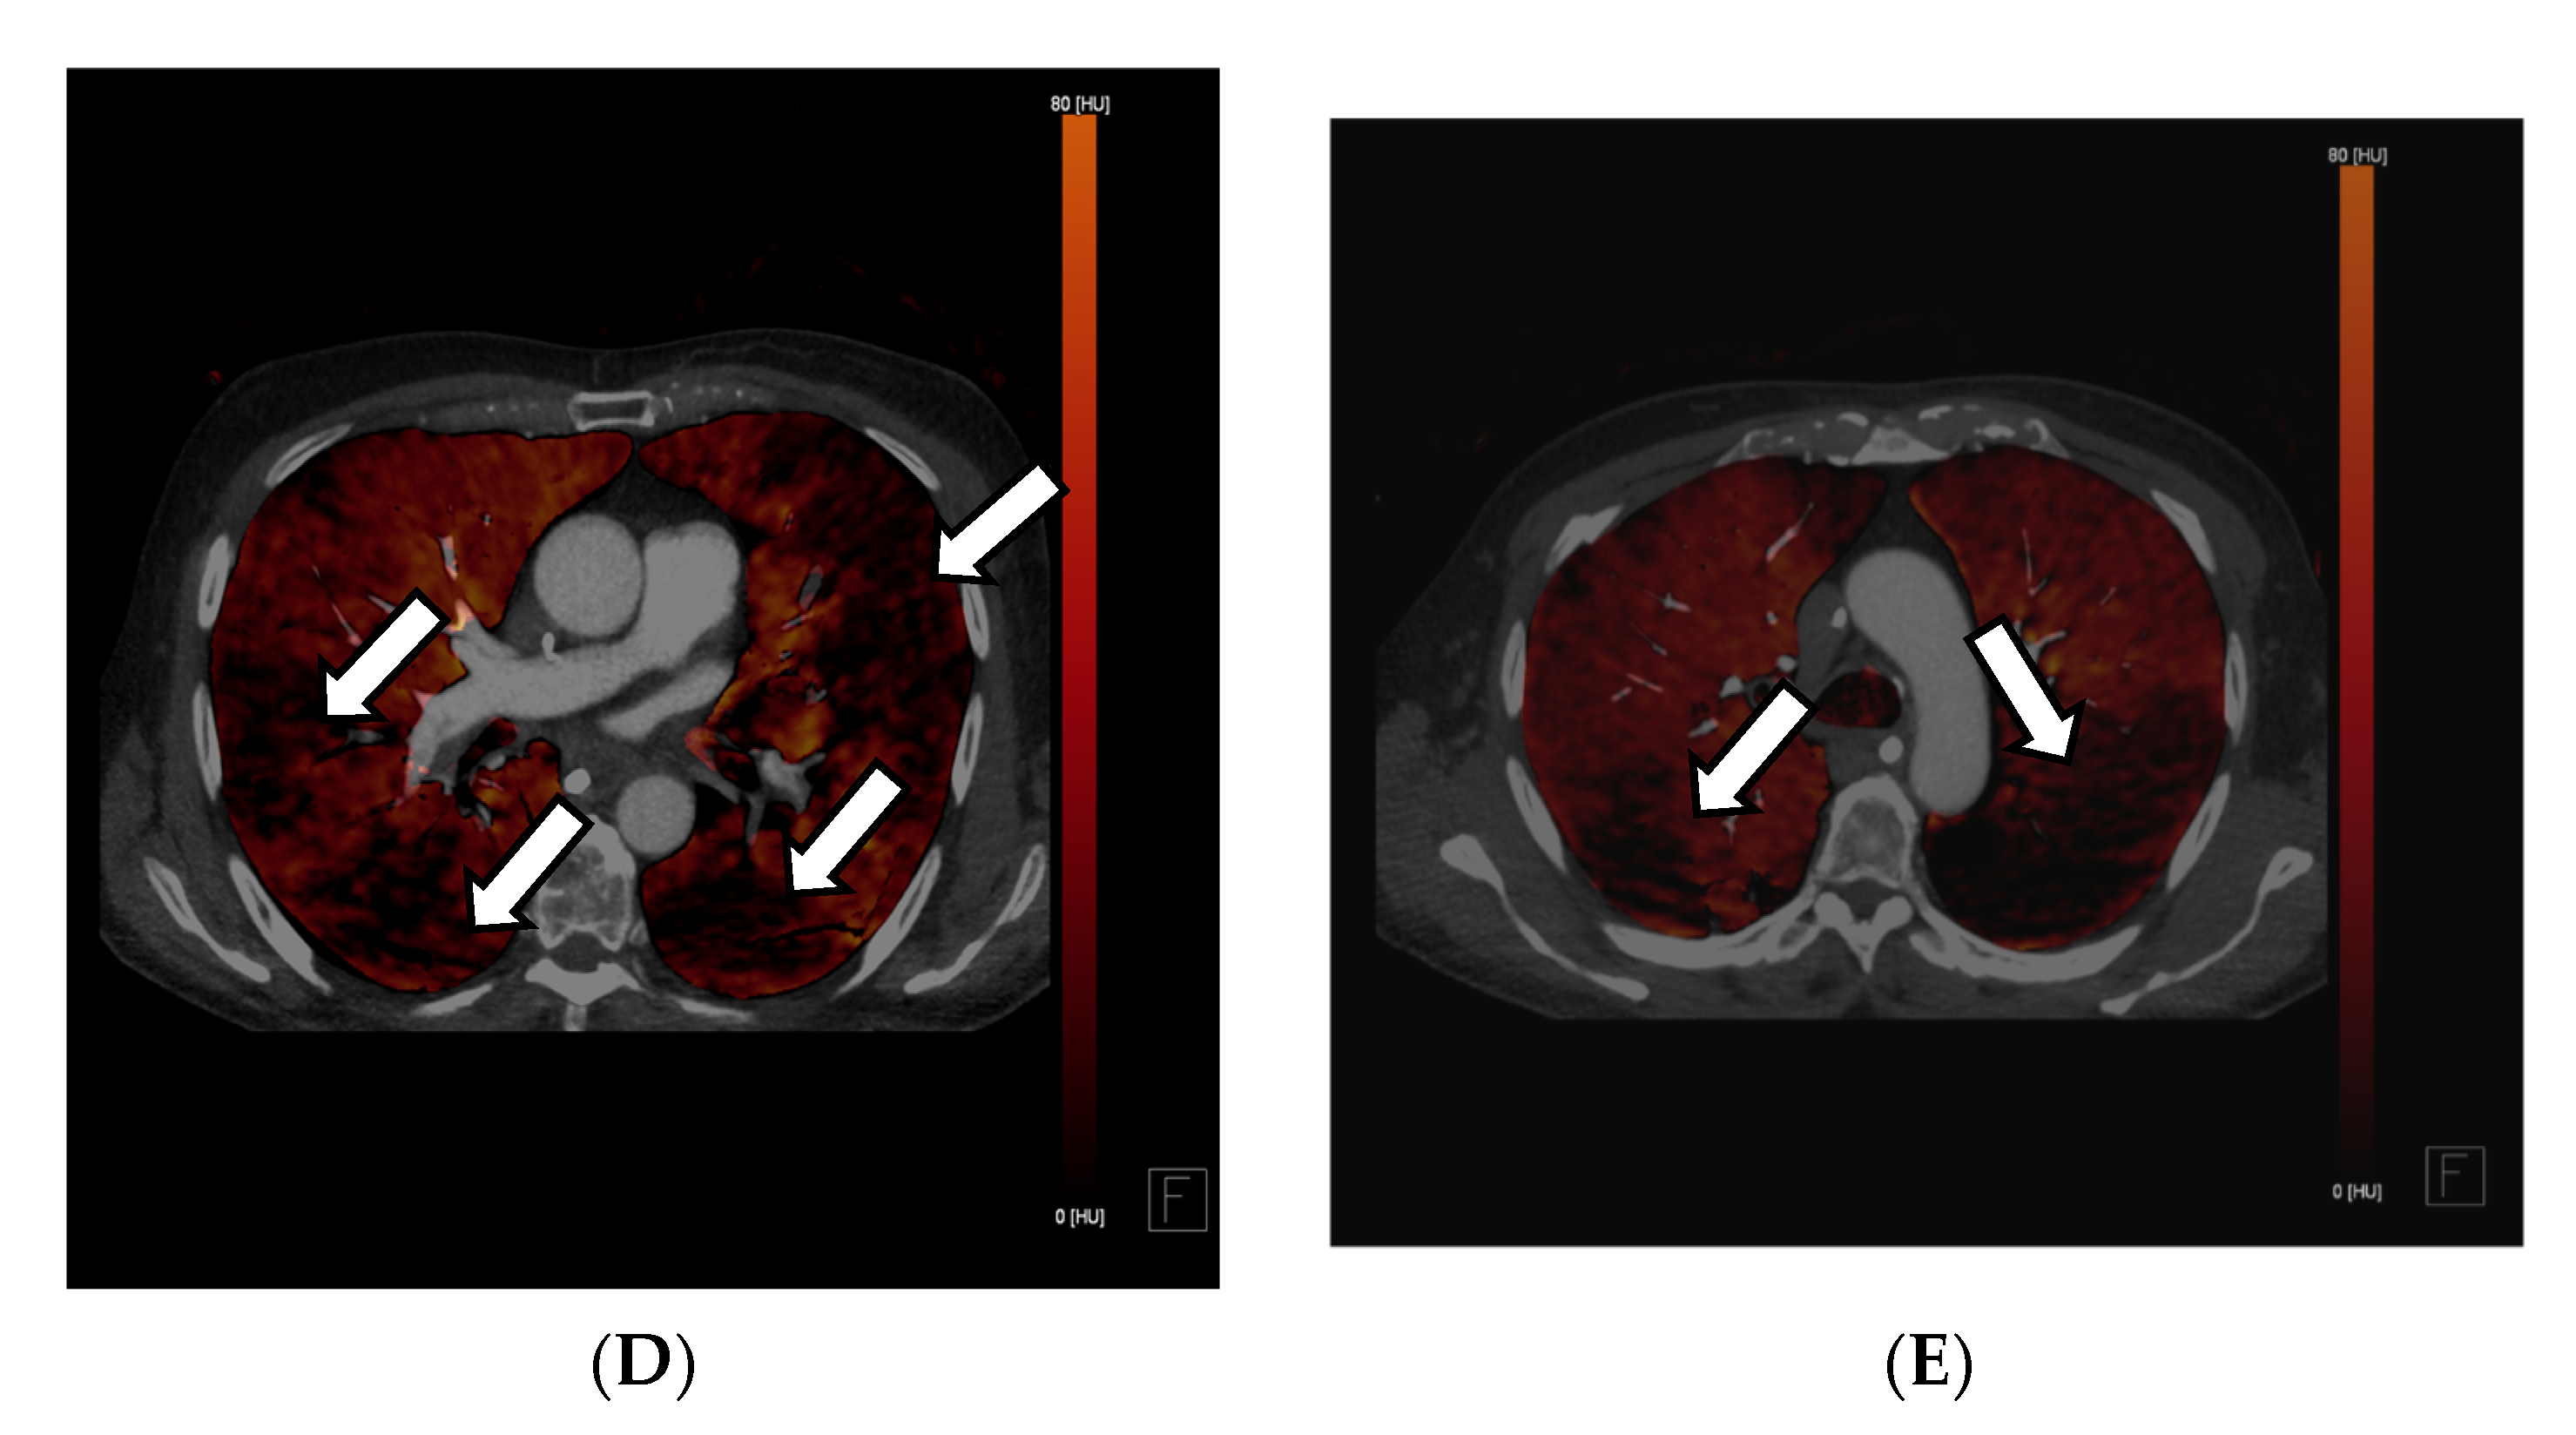

In this context, in addition to common CCTA, additional information on myocardial perfusion imaging (MPI), and thus, the functionality and prognosis of myocardial infarctions, can be derived according to Jin et al. (2016) [36]. This information can be derived from iodine images or maps, which are surrogate parameters of organ perfusion, by visualizing the amount of iodine from the contrast agent present. Kwan et al. (2021) describe that if a regional lower iodine attenuation is visible in the myocardium, it indicates myocardial infarction [36,57]. This is consistent with the method of creating iodine maps to indicate arterial lung embolism, in which the quality of DECT is essential, as the accuracy of iodine maps is directly related and proportional to the DE iodine, which is calculated by comparing the attenuation values of iodine at the two different energies. This ratio provides information about the iodine concentration within the scanned region. This means that the better the spectral separation of the high- and low-kV spectra, the less noise occurs, while the image quality of iodine maps improves, and likewise, the better the VNC images are that are created from the data. These two techniques, CCTA and myocardial perfusion, play a significant role in cardiovascular diagnostic imaging; some approaches combine both in one examination (see Figure 3A–D). Despite very promising results regarding specificity and sensitivity, false-positive CCTA MPIs can occur, which might be explained by possible artifacts from beam hardening or high iodine quantities in the heart, causing inaccurate perfusion maps [58]. As discussed above, the quality of the DECT examination is responsible for achieving a good DE iodine ratio. If the scan protocol, hardware, or patient positioning in the central FOV is insufficient, this can severely impact the image quality, thus affecting the reliability of the perfusion images, which limits the impact of MPI for clinical usage. According to Albrecht et al. (2018), the findings should be cautiously assessed and related to each patient’s clinical symptoms, similar to hybrid positron emission tomography and SPECT/CCTA studies. Still, it was proven that coronary artery CT of the heart using the latest generation MDCT has a diagnostic accuracy similar to that of invasive coronary angiography [58]. For the detection of chronic and acute abnormalities of the coronary arteries, an ECG-triggered CT of the heart can be highly accurate; however, such as in any CTA, the contrast can be insufficient due to several issues. One reason may be the insufficient concentration of iodine contrast in the vessel at the acquisition time. It can be an additional problem in systems with small detectors, which must acquire 2–3 different CT volumes in the diastole of heart action. The acquisition of a combined CT scan can take up to three heartbeats; thus, a short bolus can lead to missing the maximum contrast concentration in all or several volumes, leading to a decreased diagnostic validity of the study. In the context of coronary atherosclerosis, even small plaques can cause a difference in the perfusion of the myocardium. In conventional cardiac CT, blooming artifacts can lead to over- or after-subtraction techniques, even to underestimation of the obstruction of the lumen [57].

Figure 3.

Exemplary cardiac application of DECT in a patient admitted to the emergency chest pain unit suffering from acute angina pectoris symptoms with troponin and CK-MB elevation. The acquisition of a 120/80 kV third-generation dual-source DECT showed occlusion of the right interventricular artery (RIVA) in the CCTA (A). In the axial soft tissue kernel reconstruction, the interventricular septum and the myocardium of the left ventricle showed mild hypodensity at a closer look (B). Additionally, iodine perfusion maps were calculated from the data, revealing a myocardial perfusion deficit of the anterolateral wall and parts of the anterior septum (C–E). These findings correlate to signs of an anterolateral myocardial infarction, also reported in the ECG in the emergency room.